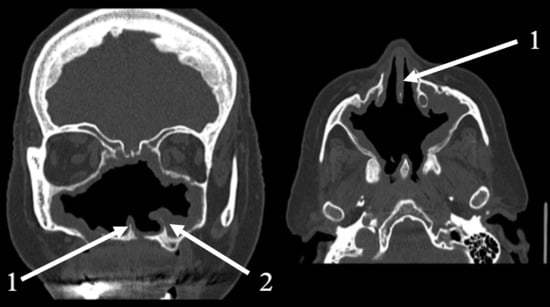

2.2. Clinical and Radiological Findings (2024)

| Late September 2022 | Disease progression | CT scan reveals an “osteolytic process”. A major Polysinusotomy with necrosectomy is performed under general anesthesia, involving extensive removal of necrotic bone and tissue. The second histopathology report confirms the findings of necrotic tissue and bone fragments, with no evidence of fungal invasion or granylomatosis. |

| 2024 | Secondary atrophic rhinitis | Endoscopy, CT scan. Treatment initiation. 3-month follow-up. |